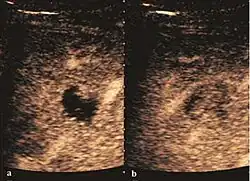

Hydatid liver cyst. Diagnostic criteria are the presence of membranes and sediment inside.